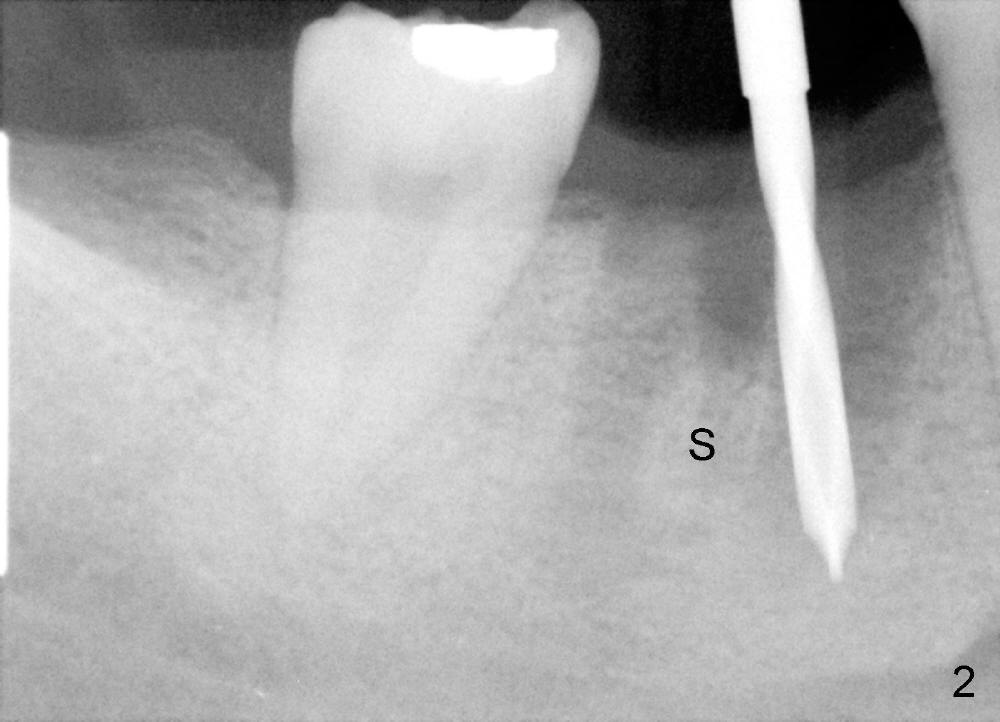

The socket of #30 heals one month after extraction (Fig.1 *). What is unexpected is that the alveolus has started to shrink (follows arrowheads). It is also unexpectedly easy to tap in RT2 (flapless). With insertion of a 2.0 mm pilot drill, PA reveals that osteotomy is not inside the septum (Fig.2 S). Redirecting osteotomy with the same pilot drill leads to insertion into the septum, but the upper end of the pilot drill should be moved mesially in next steps (arrow). With that and treatment plan in mind, combination of osteotomes, Bicon reamers and taps results in right trajectory (Fig.4 * (5x20 tapered tap), Fig.5 (6x17 tapered tap)). Harvested bone (Fig.6) is transferred to the mesial socket and condensed (Fig.7). Insertion torque of 6x17 mm implant is more than 60 Ncm. The lower end of the implant remains in the center of the septum (Fig.8 <). The gingiva contacts the implant tightly (Fig.9, 10) except mesiobucally (Fig.9 <). Periodontal dressing is used to protect the wound (Fig.11,12).